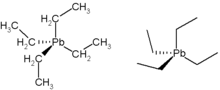

Lead forms a variety of compounds and exists in the environment in various forms.[25] Features of poisoning differ depending on whether the agent is an organic compound (one that contains carbon), or an inorganic one.[26] Organic lead poisoning is now very rare, because countries across the world have phased out the use of organic lead compounds as gasoline additives, but such compounds are still used in industrial settings.[26] Organic lead compounds, which cross the skin and respiratory tract easily, affect the central nervous system predominantly.[26]

Tetraethyllead was first added to gasoline in 1923, as it helped prevent engine knocking. Automotive exhaust represented a major way for lead to be inhaled, invade the bloodstream and pass into the brain.[145]

The use of lead in gasoline peaked in the 1970s. By the next decade most high-income countries prohibited the use of leaded petrol. As late as 2002, almost all low- and middle-income countries, including some OECD members, still used it. The UN Environment Programme (UNEP) thus launched a campaign in 2002 to eliminate its use, leading to Algeria being the last country to stop its use in July 2021.[146]

The lead ion has a lone pair in its electronic structure, which can result in a distortion in the coordination of ligands, and in 2007 was hypothesized to be important in lead poisoning's effects on enzymes (see Lone pair § Unusual lone pairs).[186]

One of the main causes for the pathology of lead is that it interferes with the activity of an essential enzyme called delta-aminolevulinic acid dehydratase, or ALAD (see image of the enzyme structure), which is important in the biosynthesis of heme, the cofactor found in hemoglobin.[187][188][189] Lead also inhibits the enzyme ferrochelatase, another enzyme involved in the formation of heme.[23][190] Ferrochelatase catalyzes the joining of protoporphyrin and Fe2+ to form heme.[23][30] Lead's interference with heme synthesis results in production of zinc protoporphyrin and the development of anemia.[191] Another effect of lead's interference with heme synthesis is the buildup of heme precursors, such as aminolevulinic acid, which may be directly or indirectly harmful to neurons.[192] Elevation of aminolevulinic acid results in lead poisoning having symptoms similar to acute porphyria.[193][194][195][196][197]